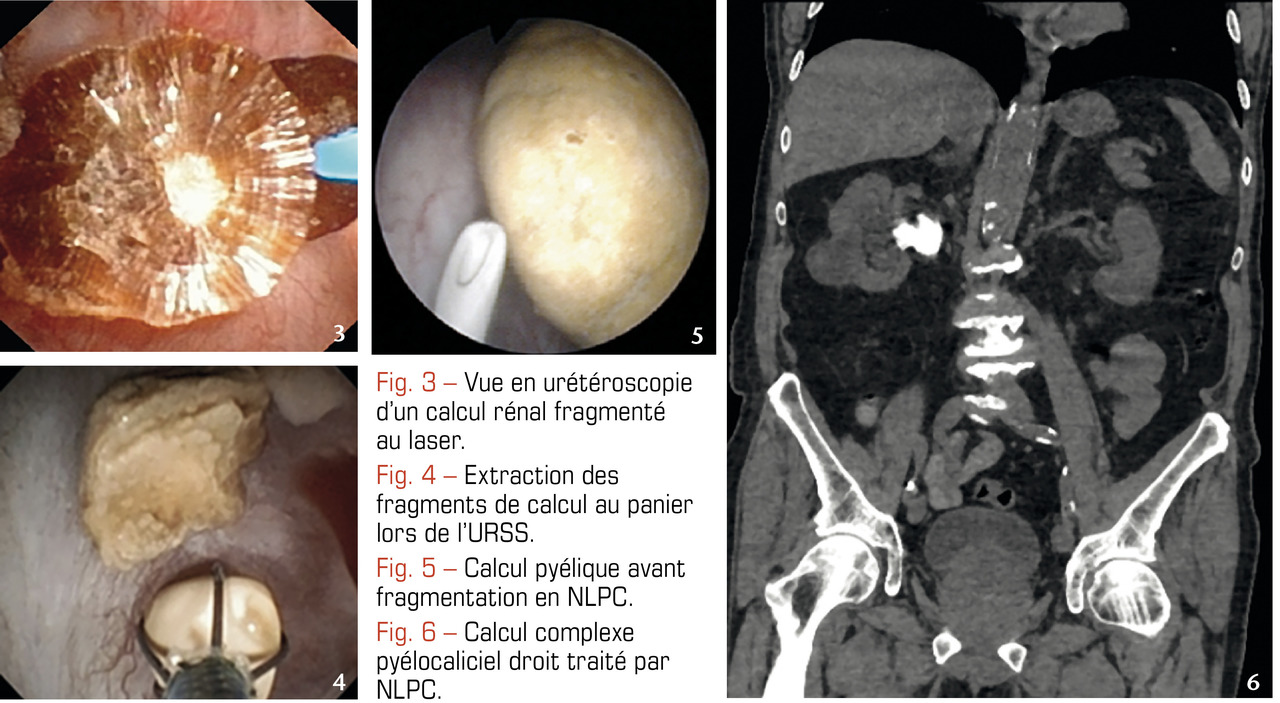

L’URS est réalisée avec des urétéroscopes métalliques de 2-3 mm de diamètre permettant d’accéder à l’uretère. L’URSS est pratiquée avec des urétéroscopes souples, fibrés ou numériques, de moins de 3 mm de diamètre atteignant les cavités rénales par voie rétrograde afin d’extraire le calcul à la pince. Associées à la fragmentation par laser, elles sont très efficaces sur ceux de moins de 2 cm, quelles que soient leur composition et leur densité au scanner (fig. 3 et 4).2-6 En effet, aucun ne résiste à l’application intracorporelle d’un laser, même si ceux dont la taille avoisine les 2 cm requièrent parfois 2, voire 3 séances. Un drainage par sonde JJ est souvent laissé en place en post-opératoire.

L’URS et l’URSS se pratiquent sous anesthésie générale et leurs indications chevauchent assez souvent celles de la LEC, au prix d’une morbidité un peu plus élevée, essentiellement infectieuse. Ces techniques ont d’ailleurs dépassé la LEC en volume d’activité depuis quelques années. Elles ne sont pas contre-indiquées en cas d’obésité et peuvent être proposées aux patients sous anti-agrégants, voire anticoagulants.2, 5 L’URSS permet également de traiter les calculs situés dans des reins malformés.

La NLPC consiste à introduire un néphroscope dans le rein à travers la paroi postérieure de l’abdomen par un tunnel mesurant 5 à 10 mm de diamètre. La fragmentation, effectuée par procédé endocorporel (laser ou ultrasons) est suivie de l’extraction. C’est le traitement de référence des calculs volumineux, supérieurs à 2 cm, et plus généralement complexes et coralliformes (fig. 5 et 6).

Les résultats ne sont quasiment pas corrélés à la taille de ces derniers.6 Elle peut être combinée à l’URSS dans le même temps opératoire pour en augmenter l’efficacité ou être la première étape d’une succession de traitements (les fragments résiduels, < 2 cm, peuvent être pris en charge ultérieurement par LEC ou URSS). Elle est contre-indiquée chez les patients sous anticoagulants et s’accompagne d’une morbidité essentiellement infectieuse et hémorragique. Toutefois, réalisée dans des centres experts, c’est une technique efficace et sûre.